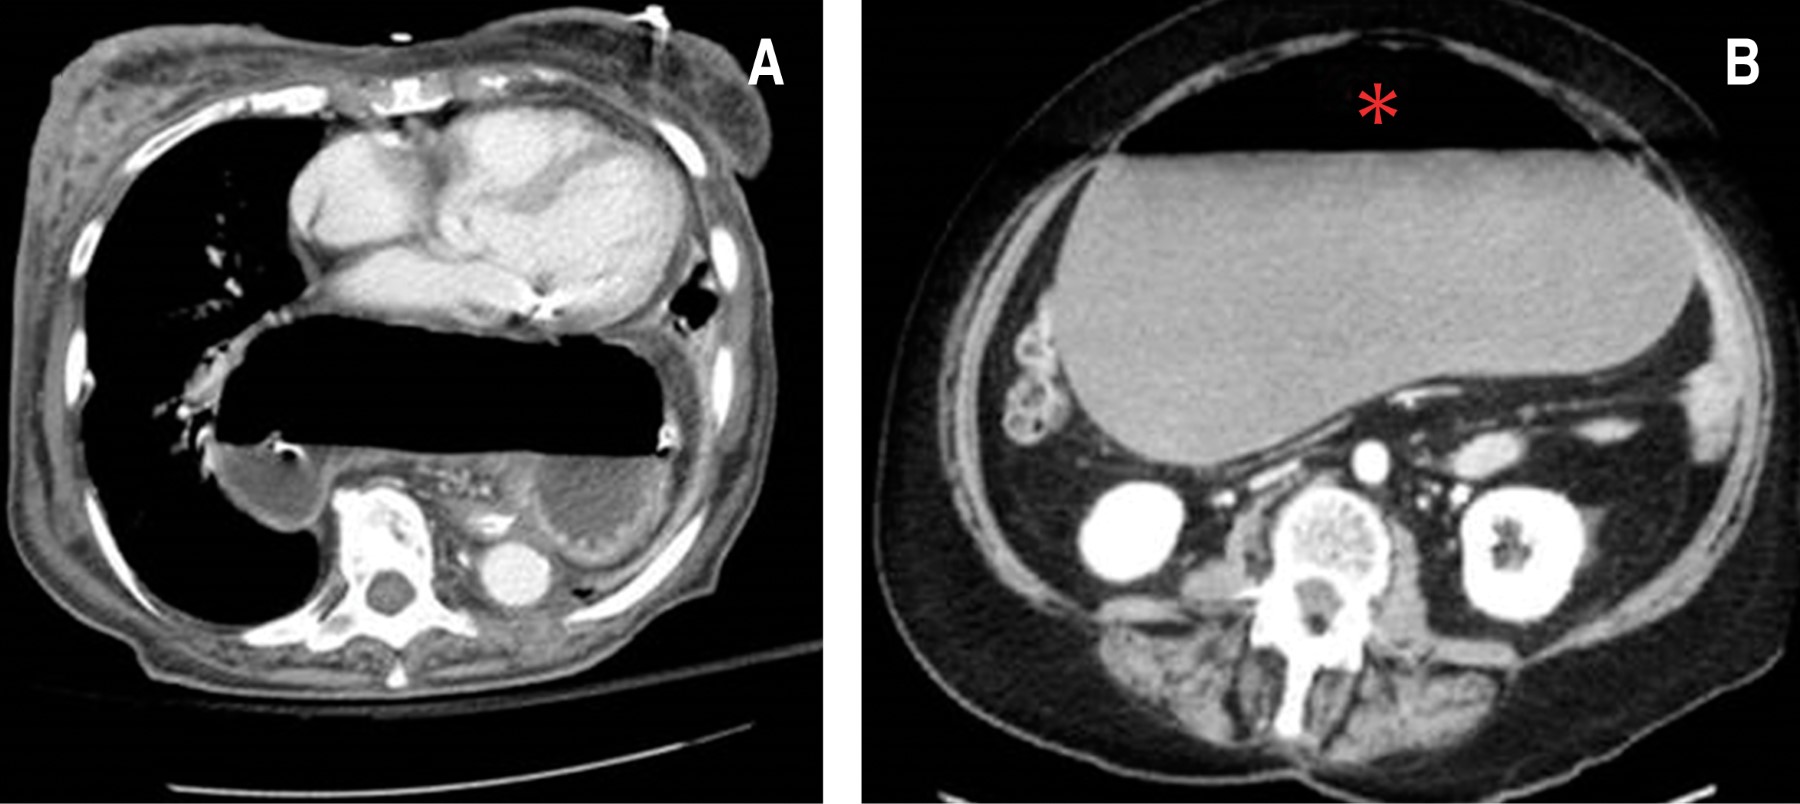

Ingresa mujer de 50 años, con diabetes tipo 2 e hipertensión arterial sin tratamiento, obesidad mórbida e histerectomía hace 20 años como antecedentes relevantes. Inició su padecimiento tres días previos a su llegada con dolor tipo cólico en epigastrio, progresivo, distensión abdominal, náusea y vómitos en múltiples ocasiones, disnea en reposo, episodios febriles no cuantificados y cinco días sin evacuar. Se registran signos vitales: tensión arterial 133/100 mmHg, frecuencia cardiaca 122 latidos por minuto, frecuencia respiratoria de 36 respiraciones por minuto, temperatura 37.7 oC. En la exploración, los campos pulmonares izquierdos estaban hipoventilados, abdomen rígido con distensión generalizada, timpánico a la percusión y dolor intenso a la palpación de predominio en epigastrio, peristalsis ausente y rebote positivo. Se inició su reanimación hídrica y se solicitaron estudios de gabinete. Con ayuda de la tomografía axial computarizada se integró un diagnóstico preoperatorio de hernia hiatal grado IV y megacolon tóxico (Figura 1). En los resultados de laboratorio: leucocitos de 16,300 células/μl, neutrófilos 14,000 células/μl, hemoglobina 17.3 g/dl, plaquetas 409,000 u/μl, gasometría arterial con lactato de 5.5 mmol/l y pH 7.48. Se hizo descompresión gástrica con sonda nasogástrica (SNG) sin dificultad para su colocación y se administró ranitidina 50 mg iv, dexametasona 8 mg iv, metoclopramida 10 mg iv, ceftriaxona 1 g iv, butilhioscina 20 mg iv, y paracetamol 1 g iv. En la laparotomía exploradora (12/07/18) se encontró una HH grado IV con VG secundario tipo II asociado con necrosis gástrica, se hizo la reducción del saco herniario y del VG, funduplicatura tipo Nissen y gastrectomía parcial con técnica de Billroth II en omega de Brown manual, con prolene aguja intestinal 3-0 en dos planos con puntos de Connell y Mayo, así como Lembert de refuerzo y plastía de hiato esofágico con prolene aguja intestinal 2-0 puntos simples y sin complicaciones al momento; se indicó esquema antibiótico con ciprofloxacino 400 mg iv, cada 12 horas por 10 días y metronidazol 500 mg iv, cada ocho horas por 10 días y fue llevada a la Unidad de Cuidados Intensivos para su recuperación. Una semana después, presentó dehiscencia del 50% de la anastomosis gastroyeyunal, con fuga de contenido gástrico. Se realizó un cierre primario gástrico con parche de Graham y se colocó bolsa de Bogotá. En los estudios de control presentó leucocitosis de 22 mil células/μl, neutrófilos 18 mil células/μl, hemoglobina 8 mg/dl, plaquetas 123 mil u/μl, pH de 7.31, lactato de 3.9 mmol/l, falla renal asociada con creatinina de 3.2 mg/dl, urea de 65 mg/dl, nitrógeno ureico 45 mg/dl, sodio 153 mEq/l, potasio 2.8 mEq/l, cloro 110 mEq/l; después, y debido a la persistencia de la fuga, se hizo un aseo quirúrgico con gastrectomía parcial y anastomosis gastroyeyunal en Y de Roux en dos planos con puntos de Connell y Mayo y refuerzo de puntos Lembert con prolene aguja intestinal 3-0, posterior yeyunostomía utilizando seda 2-0 con puntos simples a aponeurosis de pared abdominal. En las siguientes semanas se sometió a cuatro aseos quirúrgicos, recambio de bolsa de Bogotá y gastrostomía tipo Stamm debido a fuga intestinal. Persistió con cuadro de sepsis abdominal, evolucionó con perforación de la anastomosis y se colocó sonda T gástrica, encontrándose la cavidad con abundante material purulento y fétido, además de abdomen congelado. Durante su estancia se manejó con antibioticoterapia múltiple con ciprofloxacino y metronidazol, cambiando a meropenem 500 mg iv, cada ocho horas y posterior ajuste a tigeciclina 100 mg iv, continuando con 50 mg iv, cada 12 horas y vancomicina 1 g iv, cada 12 horas por 10 días, además de nutrición parental total, sin presentar mejoría. Por cultivos de líquido peritoneal positivos a Staphylococcus aureus y Acinetobacter baumannii multirresistentes, obesidad mórbida y estado nutricional deficiente, desarrolló un choque séptico de foco abdominal, sin respuesta a medidas de reanimación, falleciendo un mes después de su ingreso.

Figura 1